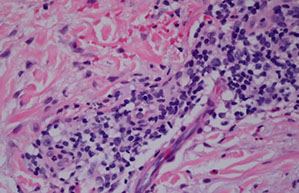

Micro: Subepidermal blister (bullae) c eos and sometimes neutros in blister cavity

- can see eos lined up on DE junction in urticarial lesions

IF: Direct IF in perilesional tissue shows IgG and C3 on DE junction (basement membrane) in linear or n-serrated pattern

- Indirect has positivity on the roof of the lesion (vs on the floor in epidermolysis bullosa acquisita)

Bullous pemphigoid